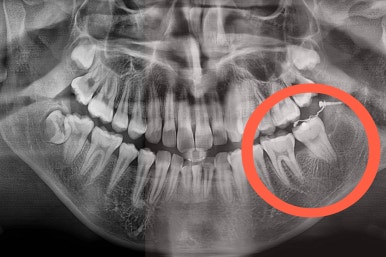

구멍이 뻥 뚫린게 보이실거에요.

매복 사랑니를 발치한 자리입니다.

사랑니를 발치하며 앞쪽에 살려 써야하는 어금니에 작은 장치를 부착했어요.

어금니를 당겨줄 미니스크류도 사랑니를 발치하면서 식립해 주었어요.

사랑니 뽑은 자리가 매우 커보이는데요.

보통은 3~6개월 지나면 뼈가 차오른답니다.

매복치아였기 때문에 입 안에서는 장치도 거의 보이질 않죠.

해당 장치와 미니스크류 사이에 교정용 고무줄을 연결하여 지속적으로 당겨줍니다.